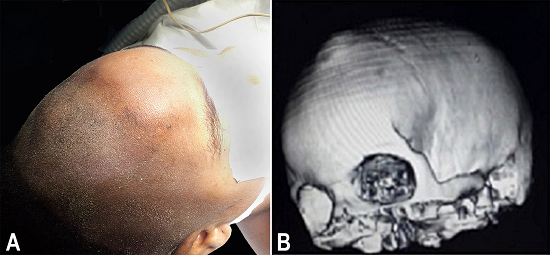

A 17-year-old female patient attended the neurosurgery department complaining of a palpable mass in the left frontal bone as well as headaches and seizures since the age of 8 years. She was born after a normal labor. Nine years later, when she attended the clinic, a physical exam was undertaken that revealed a firm and rounded palpable mass at the left frontal bone (Figure 1A).

On neurological exam, the patient had no focal signs. She had normal mental status and vital signs. She was conscious, and her pupillary reflex to light was normal, as were the muscular force, the deep tendon reflexes, and her sensibility. The computed tomography (CT) scan of her head showed a left frontal bone a protrusion (Figure 1B).